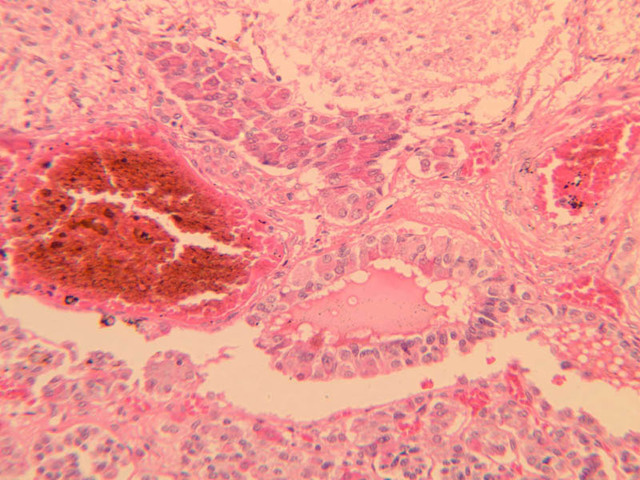

The thyroid gland (slide B-51, lead hematoxylin [10x, 20x, 40x, 40x]; B-52, H&E [10x-labeled, 20x, 40x-labeled, 40x]; B-53, PAS [2.5x, 10x, 20x, 40x]) consists of many closely packed, roughly spherical structures known as follicles, which are enclosed in a thick connective tissue capsule. Connective tissue septa extend from the capsule into the substance of the gland, carrying numerous blood vessels. Follicular cells are arranged as shells of simple cuboidal epithelium surrounding a gelatinous mass known as colloid. Look for a ring of epithelial cells around the homogeneous, pink-staining colloid. The cytoplasm of the follicular cells (principal cells) is faintly basophilic. The follicular cells secrete thyroglobulin, a glycoprotein, which is stored extracellularly in the colloid. In response to TSH, the follicular cells endocytose the colloid and hydrolyze it to form thyroxine. You can see where colloid has been resorbed because this process leaves small holes in the colloid adjacent to the follicular cells. These holes are known as resorption lacunae (B-52 [10x, 20x, 40xlabeled]). Very active follicles may exhibit a columnar epithelium and increased numbers of resorption lacunae. Between follicles, the stroma of the thyroid gland consists of a thin layer of connective tissue and a rich capillary network. Parafollicular cells (light cells or C cells) are located in the connective tissue between follicles or adjacent to follicular cells within follicles. When they lie within the follicular wall, the parafollicular cells do not reach the lumen. Parafollicular cells are slightly larger than the follicular cells and, in H & E preparations, have a more lightly stained cytoplasm (B-52, H&E [10x, 20x, 40x-labeled] [10x-labeled, 20x, 40x-labeled] [10x, 20x, 40x] [10x, 20x, 40x]; B-53, PAS [10x, 20x, 40x]). Parafollicular cells are readily identifiable in slide B-51 (stained with lead hematoxylin), where they appear as purplish-black structures in which the nuclei are difficult to discern (B-51 [10x, 20x, 40x-labeled]). These cells secrete calcitonin, which lowers serum calcium levels by inhibiting bone resorption and accelerating osteoid calcification.